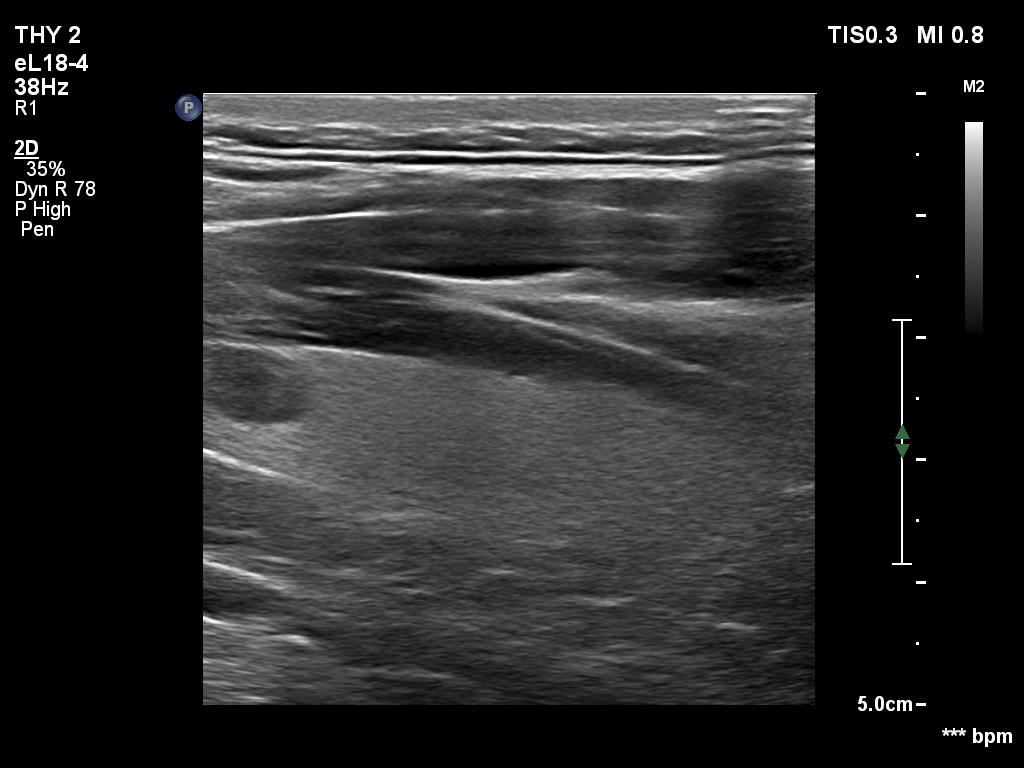

Ultrasonography. The thyroid was echonormal and had two cystic lesions in the left lobe. With higher frequency, the dorsal part of both lobes presented with hypoechoic blurred areas. With frequency decreased, these areas have disappeared.

Comment. This case illustrated the well-known inverse relation between penetrance and resolution. Better the former worst the latter and conversely. This has particular and practical importance if we examine obese patients using high-end equipment with high frequency. In such patients the obesity can significantly worsen the penetrance. This can be solved by decreasing the frequency and remove all software harmonization.